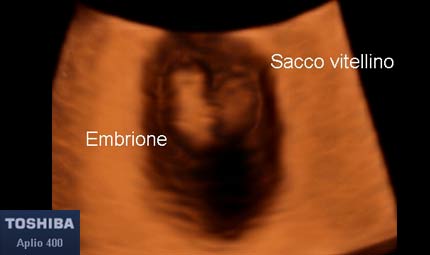

L'embrione è lungo dai 2 ai 4 millimetri. Sebbene assomigli ancora un po’ a un girino, dal tronco dell’embrione spuntano già i germogli degli arti e si vedono due macchie scure ai lati della testa che diventeranno più avanti gli occhi. Il sistema nervoso centrale si sta già formando e permette all’embrione di compiere i primi movimenti, anche se saranno percepibili solo più avanti nella gravidanza.

Sett 6, embrione e sacco vitellino © Dr. Maurizio Longo, DIAGNOSTICA PRENATALE